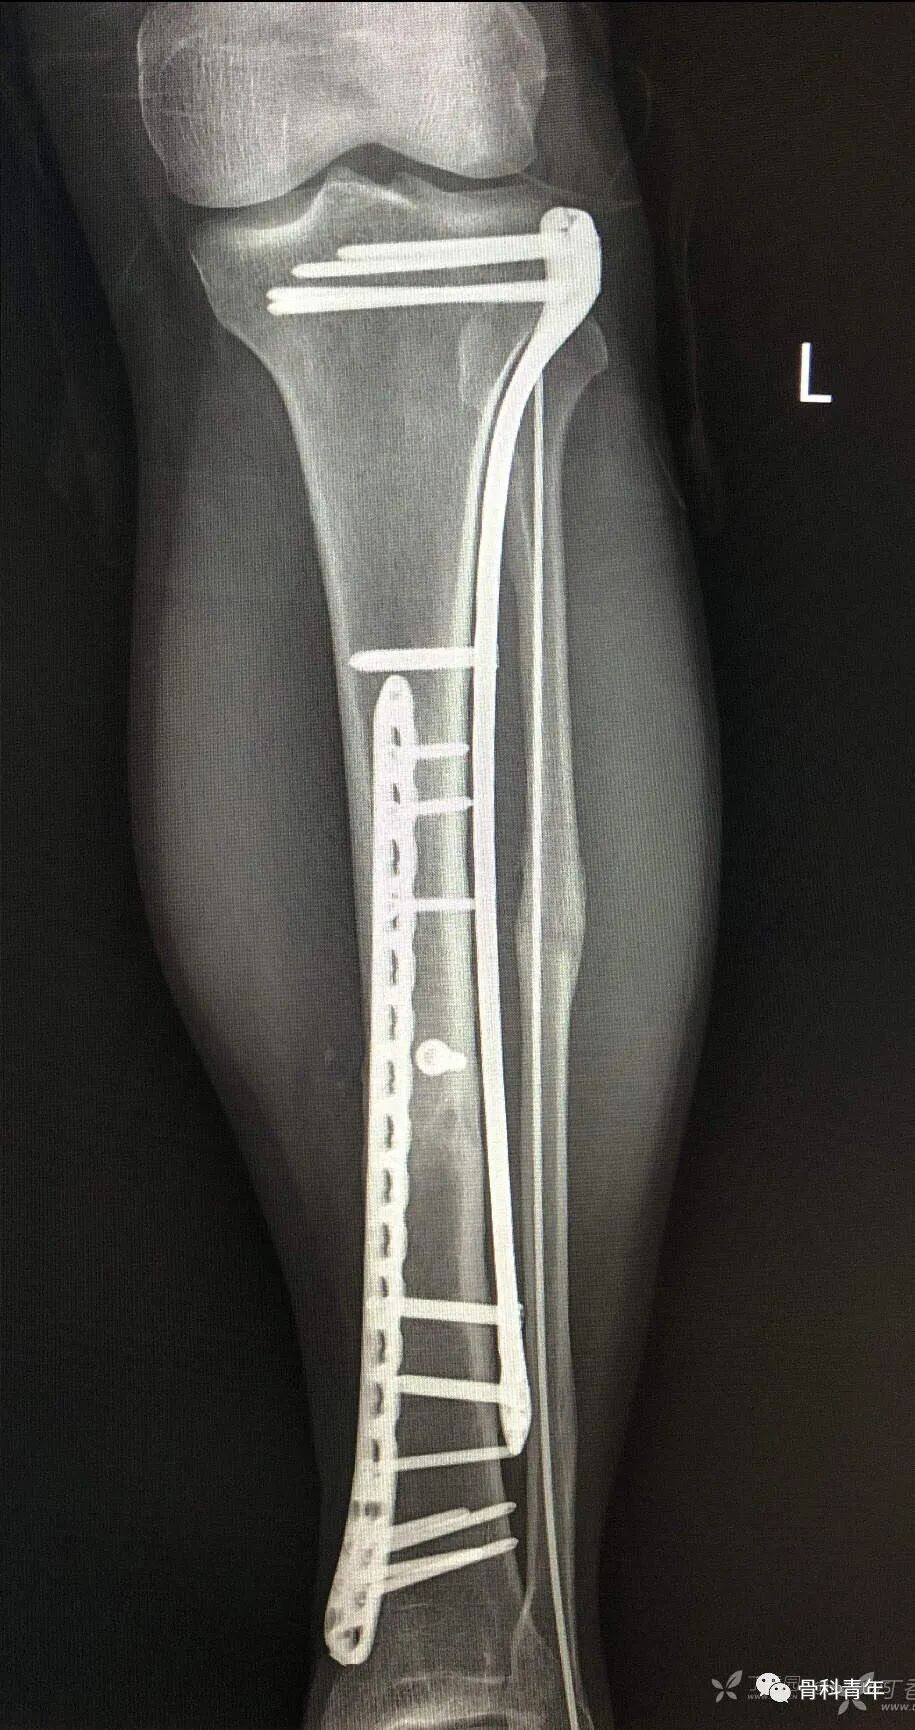

10.胫骨骨折(钢板)